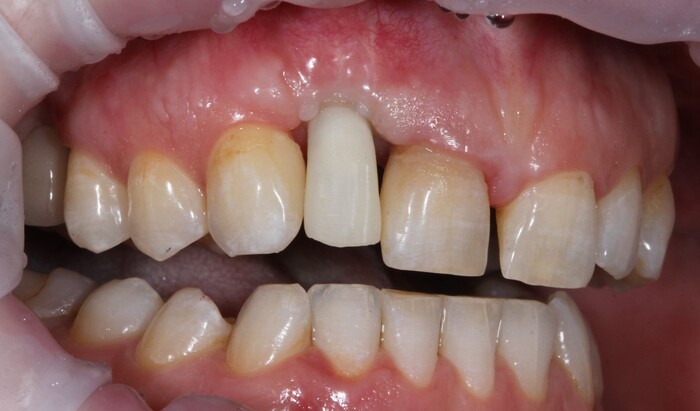

Еще через пару месяцев временную коронку сняли для изготовления новой:

И вот картинка спустя полгода «ношения» новой временной коронки: